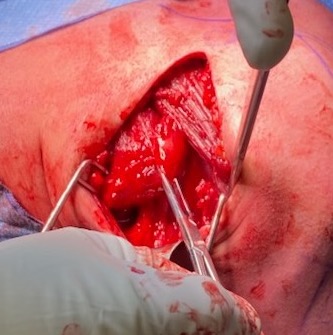

Right shoulder, with Hohmann retractor exposing humerus

Bone trough with sutures passed through lateral drill holes